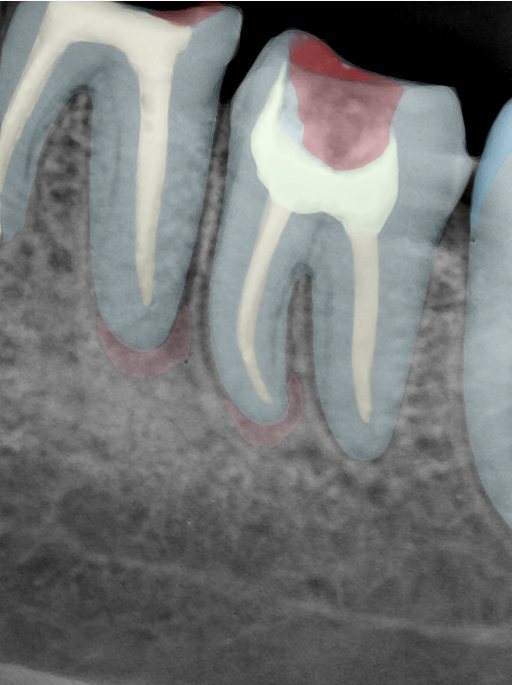

CR/DR 牙齿分割阶段记录

当前进展

- 完成了 CR/DR 牙齿相关分割训练

- 当前结果已经达到阶段预期,但仍有细节问题需要继续处理

相关测试

遇到的问题

- 训练过程中出现过 mask 下移问题

- 部分结果会出现 box 填充异常

- mask 边缘仍然有比较明显的锯齿感

第二版算法问题测试

结论:修复类出现了不鲁棒的情况,后续需要加入轮廓的扩充数据进行增强。